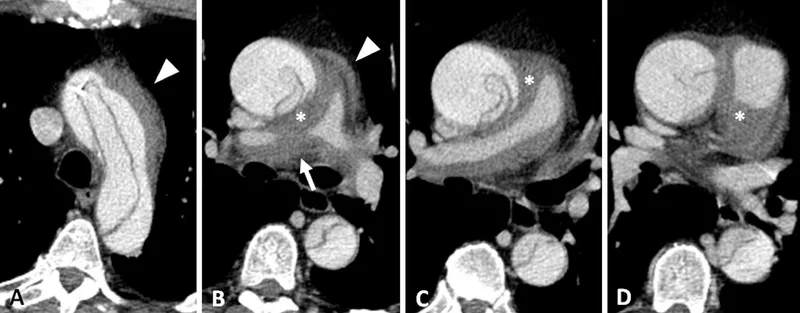

- Aortic & Great Vessel Injury:

- Mechanisms: Deceleration, penetrating.

- 📌 CT Signs: Direct (Intimal flap, Pseudoaneurysm, Active extravasation, Irregular contour); Indirect (Mediastinal hematoma >1cm, periaortic hematoma).

- Cardiac Injury: Blunt Cardiac Injury (BCI) spectrum. Tamponade risk. CT: pericardial effusion, myocardial hematoma.